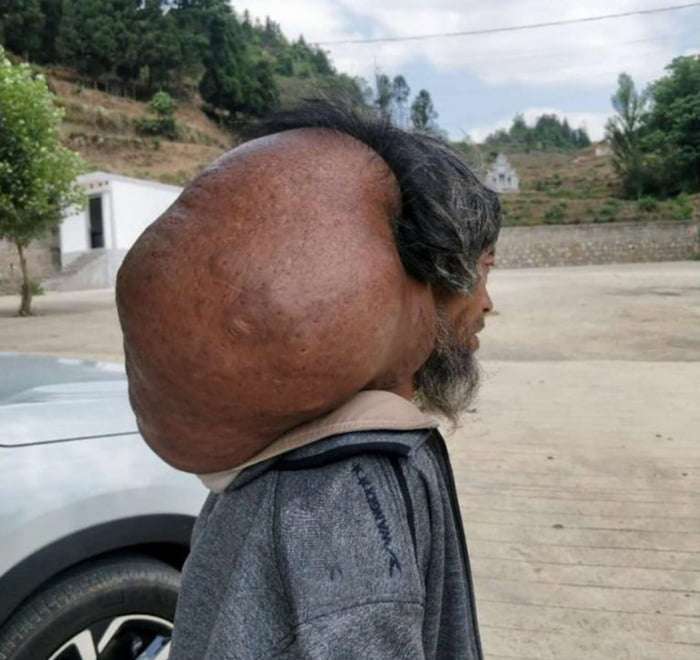

15公斤腫瘤如影隨行47年 醫生花10小時幫他移除「瞬間超不習慣」

2018年06月04日大陸貴州有一位64歲的趙姓老伯,他17歲時頸上出現一個腫瘤,腫瘤越長越大,足足長到了15公斤。這麼多年來,他一直背著這個沉重的負擔生活。最近,他終於解脫了。

▼趙老伯表示,他17歲時頸上出現了腫瘤,剛開始只是雞蛋大小,因為不疼不癢,他就沒有在意。隨著時間的推移,腫瘤越來越大,開始影響他的生活。他只能側身睡覺,沒辦法穿套頭衣物,洗澡也需要家人幫忙。

▼趙老伯家經濟條件不好,一直沒有接受治療,但頭頸托著15公斤的重量,真的太吃力了。眼看腫瘤越變越大,孩子們擔心他受不了,這才籌錢帶他去看病。醫生看到後驚呼:「我工作這麼多年,從來沒見過這麼大的腫瘤!」

▼貴州省腫瘤醫院綜合外科副主任董世祥表示,趙老伯頸上的腫瘤,初步診斷是脂肪瘤。「患者的情況不是典型的脂肪瘤,並不是每個人的脂肪瘤都會長這麼大,還是要視個人情況而定。」

▼經過10個小時的手術,醫生幫趙老伯切除95%的腫瘤,他終於不用再受苦了。

背負了47年的負擔一下子卸掉,趙老伯還有點不習慣。沒有腫瘤的束縛,他的生活終於回到正軌了~